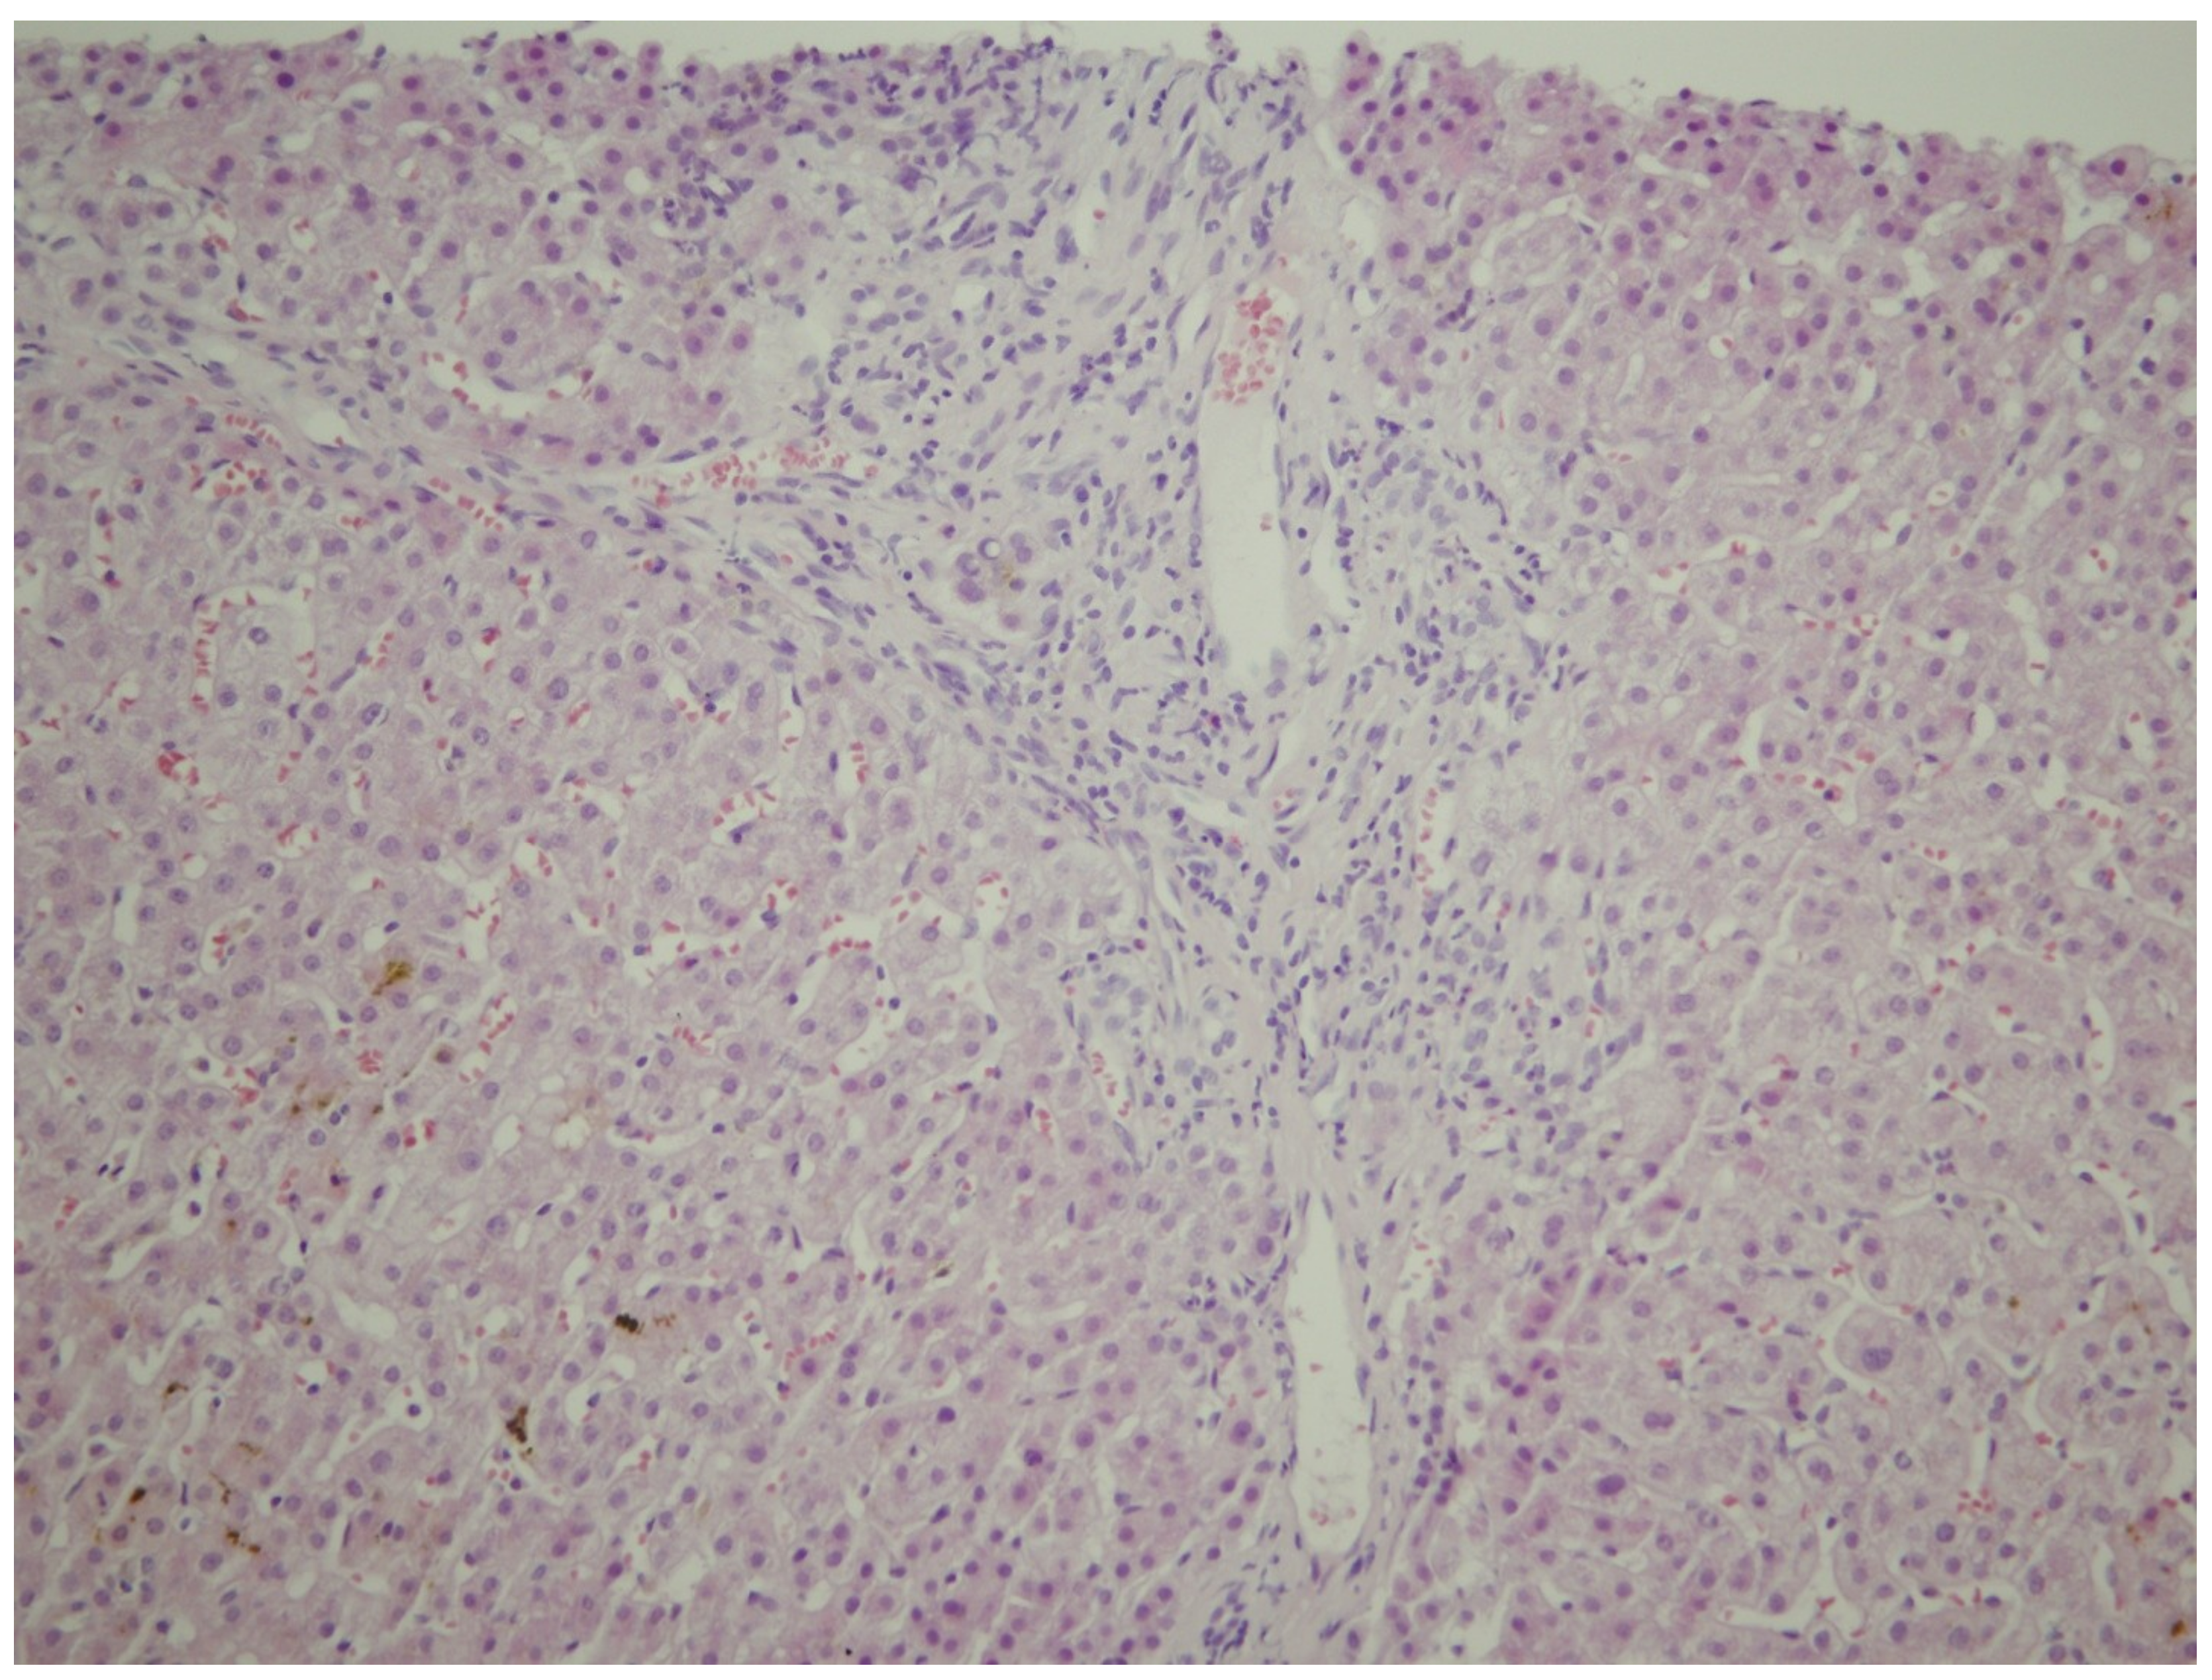

2. Case Report